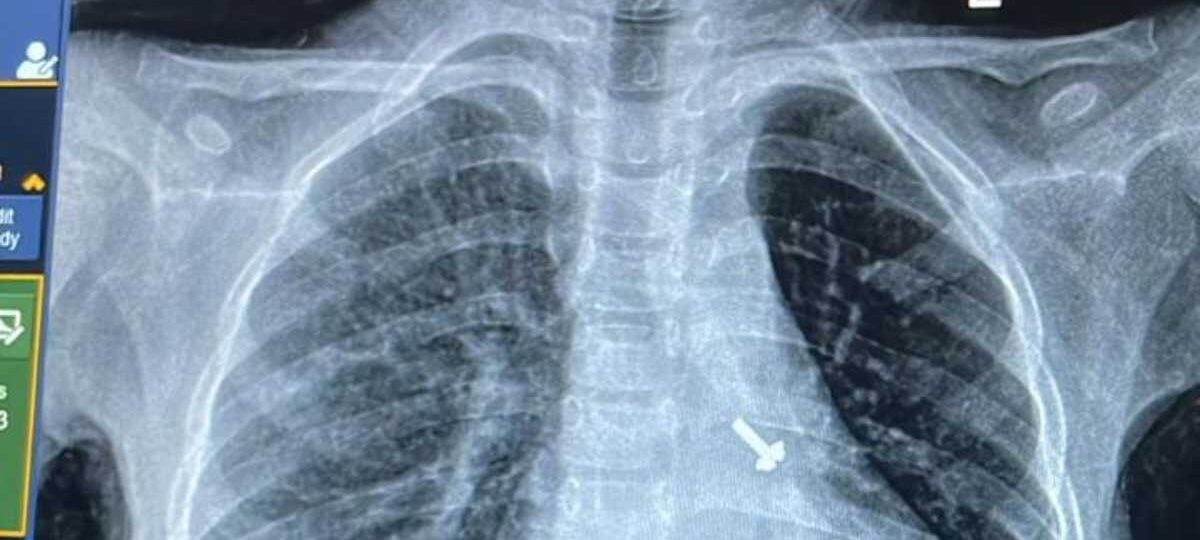

बालरोग विशेषज्ञ डॉ. व्यास कुमार राठौड़ के मुताबिक बच्चे की कुछ प्रारंभिक जांचें कराई गईं, जिसमें उसकी छाती के एक्स-रे एवं सीटी स्कैन में बच्चे के फेफड़े में एक पेंच दिखाई दिया है । इस विषय में चिकित्सक द्वारा बच्चे के अभिभावकों से पूछे जाने पर उन्हें बताया गया कि बच्चे ने घर में खेल-खेल में पेंच निगल लिया, जिसका पता परिजनों को नहीं लग पाया ।